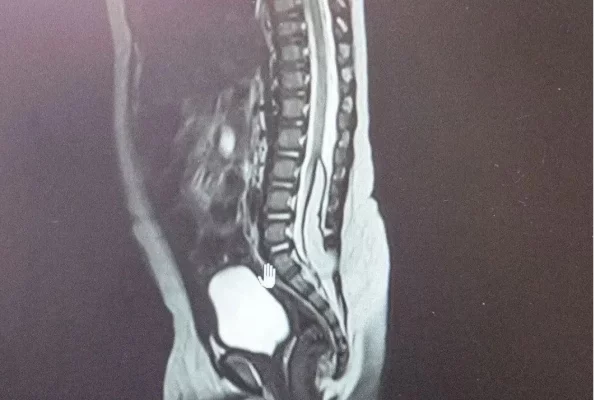

В Кемерове медики областной детской больницы с начала года спасли двух детей со сложными врождёнными аномалиями. Одному пациенту было 8 месяцев, другому – 6, рассказали в минздраве Кузбасса.

У обоих детей выявили липомиелоцеле – редкую аномалию, при которой патологическая жировая ткань формируется в спинном мозге, фиксируя его. Из-за этого нарушается развитие и рост как самого спинного мозга, так и тазовых органов, у детей происходит недержание.

В обоих случаях нейрохирурги провели сложные ювелирные операции, удалив новообразования. Теперь новорождённые могут расти и развиваться, как обычные дети.